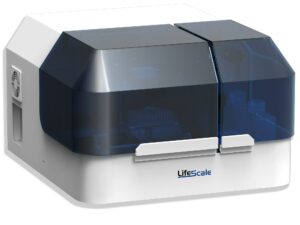

Affinity Biosensors Receives FDA Clearance for the LifeScale AST System

This milestone gives healthcare professionals an important tool for managing bacteremia by providing antibiotic susceptibility test (AST) results with unprecedented speed.

This milestone gives healthcare professionals an important tool for managing bacteremia by providing antibiotic susceptibility test (AST) results with unprecedented speed.

Benefits of the system, according to a news release, include maneuverability and visualization.

The clearance ends a three-year back-and-forth with the FDA to get the product to market.